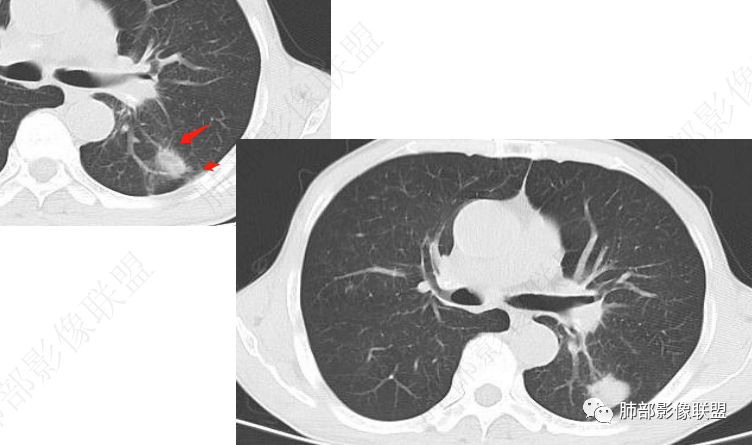

左肺及右肺中叶可见多发斑片状,条索及结节状高密度影,界不清,树芽征(+),中叶伴有支气管扩张,左肺下叶背段结节,周围伴毛刺,近端气管截断,实质密度不均匀,强化方式(看不清),8L,7及4区及左肺门见多发肿大淋巴结,老年男性,感染指标升高,呼吸道慢性病史,二元论,结核+左肺下叶背段恶性结节(鳞癌?)左肺下叶后基底段有新发感染?

左肺下叶沿支气管束走形实性病灶,增强后不均匀强化,低密度坏死或者粘液,周围肺野斑点状炎性病灶,左肺上叶尖后段及右下肺散在斑片状影。纵隔及左肺门多发肿大淋巴结。支气管镜左肺上叶舌段狭窄。首先考虑感染性病变,结核可能,鉴别肿瘤性病变,鳞癌;其次结节病。

双肺上叶斑点索条影,边缘清晰,可见树芽征。右肺中叶、左肺下叶局限性支气管扩张及索条影。左肺下叶背段结节膨胀感不强,直边,不均匀强化。左侧膈肌抬高相近肺内条片状影。纵隔及左肺门淋巴结稍增大。一元:先考虑感染性病变,NTM,努卡。两元:左下肺腺癌+淋巴结转移+膈神经麻痹。

左肺下叶不规则实性结节,无毛刺,支气管进入阻塞,周围树芽,远端长索条,左侧胸膜增厚,左肺门淋巴结略增大,右肺中叶支气管扩张,考虑炎性肉芽肿,结核、NTM,鉴别腺癌

左肺下叶不规则软组织密度影,密度不均,胸膜牵拉,环形强化,周围可见多发结节影,左侧肺体积略缩小,左肺上叶多发结节及条索,考虑结核,鉴别腺癌

左肺下叶不规则实性结节,密度不均,支气管进入阻塞,树芽,长索条,边缘强化,考虑炎性肉芽肿,结核、NTM。

左肺下叶结节影,平直为主周围散在腺泡结节,支气管扩张,临近胸膜牵拉,考虑结核鉴别腺癌

3.影像表现双肺可见多发斑片状,条索及结节状高密度影,界不清,树芽征(+),考虑肺结核问题不大。左肺下叶背段结节病灶相对另类,应当警惕结核伴肿瘤,如腺癌。该病灶边缘有刀切征,未见典型分叶毛刺,结合周围有卫星灶,胸膜增厚粘连,可疑反晕,边缘有少许的磨玻璃样改变、较模糊,病灶周围有条索、树芽,相对强化较轻微,一元论考虑肺结核可能性大。腺癌如伴有磨玻璃多为中心实性成分周围为磨玻璃成分,且病灶膨隆为主、可见分叶、毛刺、胸膜凹陷、血管集束,脐凹征等征象,本例有轻微胸膜长线牵拉凹陷但其余肺癌常见恶性征象均不明显,且出现边缘平直等明显指向良性病变的征象。